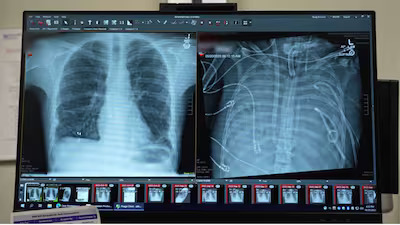

The patient was admitted in 2023 after contracting Influenza B, which progressed to acute respiratory distress syndrome (ARDS) and necrotizing pneumonia.

Despite being on a ventilator and extracorporeal membrane oxygenation (ECMO), the patient developed refractory septic shock, suffered multiple cardiac arrests, and experienced kidney failure. Doctors reported that the infection could not be controlled while the severely damaged lungs remained in his body, according to the journal Med.

Dr Ankit Bharat, chief of thoracic surgery at Northwestern University Feinberg School of Medicine, and his team performed a bilateral pneumonectomy, removing both lungs to eliminate the source of infection.

To replace lung function, the team developed a custom extracorporeal total artificial lung (TAL) system. The device oxygenated the patient’s blood, removed carbon dioxide, and helped regulate circulation to support heart function.

Dr Bharat said the patient suffered cardiac arrest shortly after arriving at the hospital but was successfully resuscitated. “He was critically ill. It was very clear that we had to do something right away,” he told Scientific American. He added that when an infection becomes so severe that the lungs are “melting,” the damage is irreversible, according to Precision Medicine.

The team then developed “artificial lungs” designed to pump blood from the right side of the patient’s heart to the left, oxygenate it, and circulate it throughout the body.

Within 48 hours, the patient’s condition began to improve, with blood pressure stabilising and kidney function returning to normal. Doctors were able to discontinue medications supporting his heart. Tests on the removed lungs later confirmed irreversible damage, underscoring the need for a transplant.

The patient was placed on the waiting list for a double-lung transplant and received donor organs shortly afterward. More than two years later, he has normal lung function and shows no signs of organ rejection.